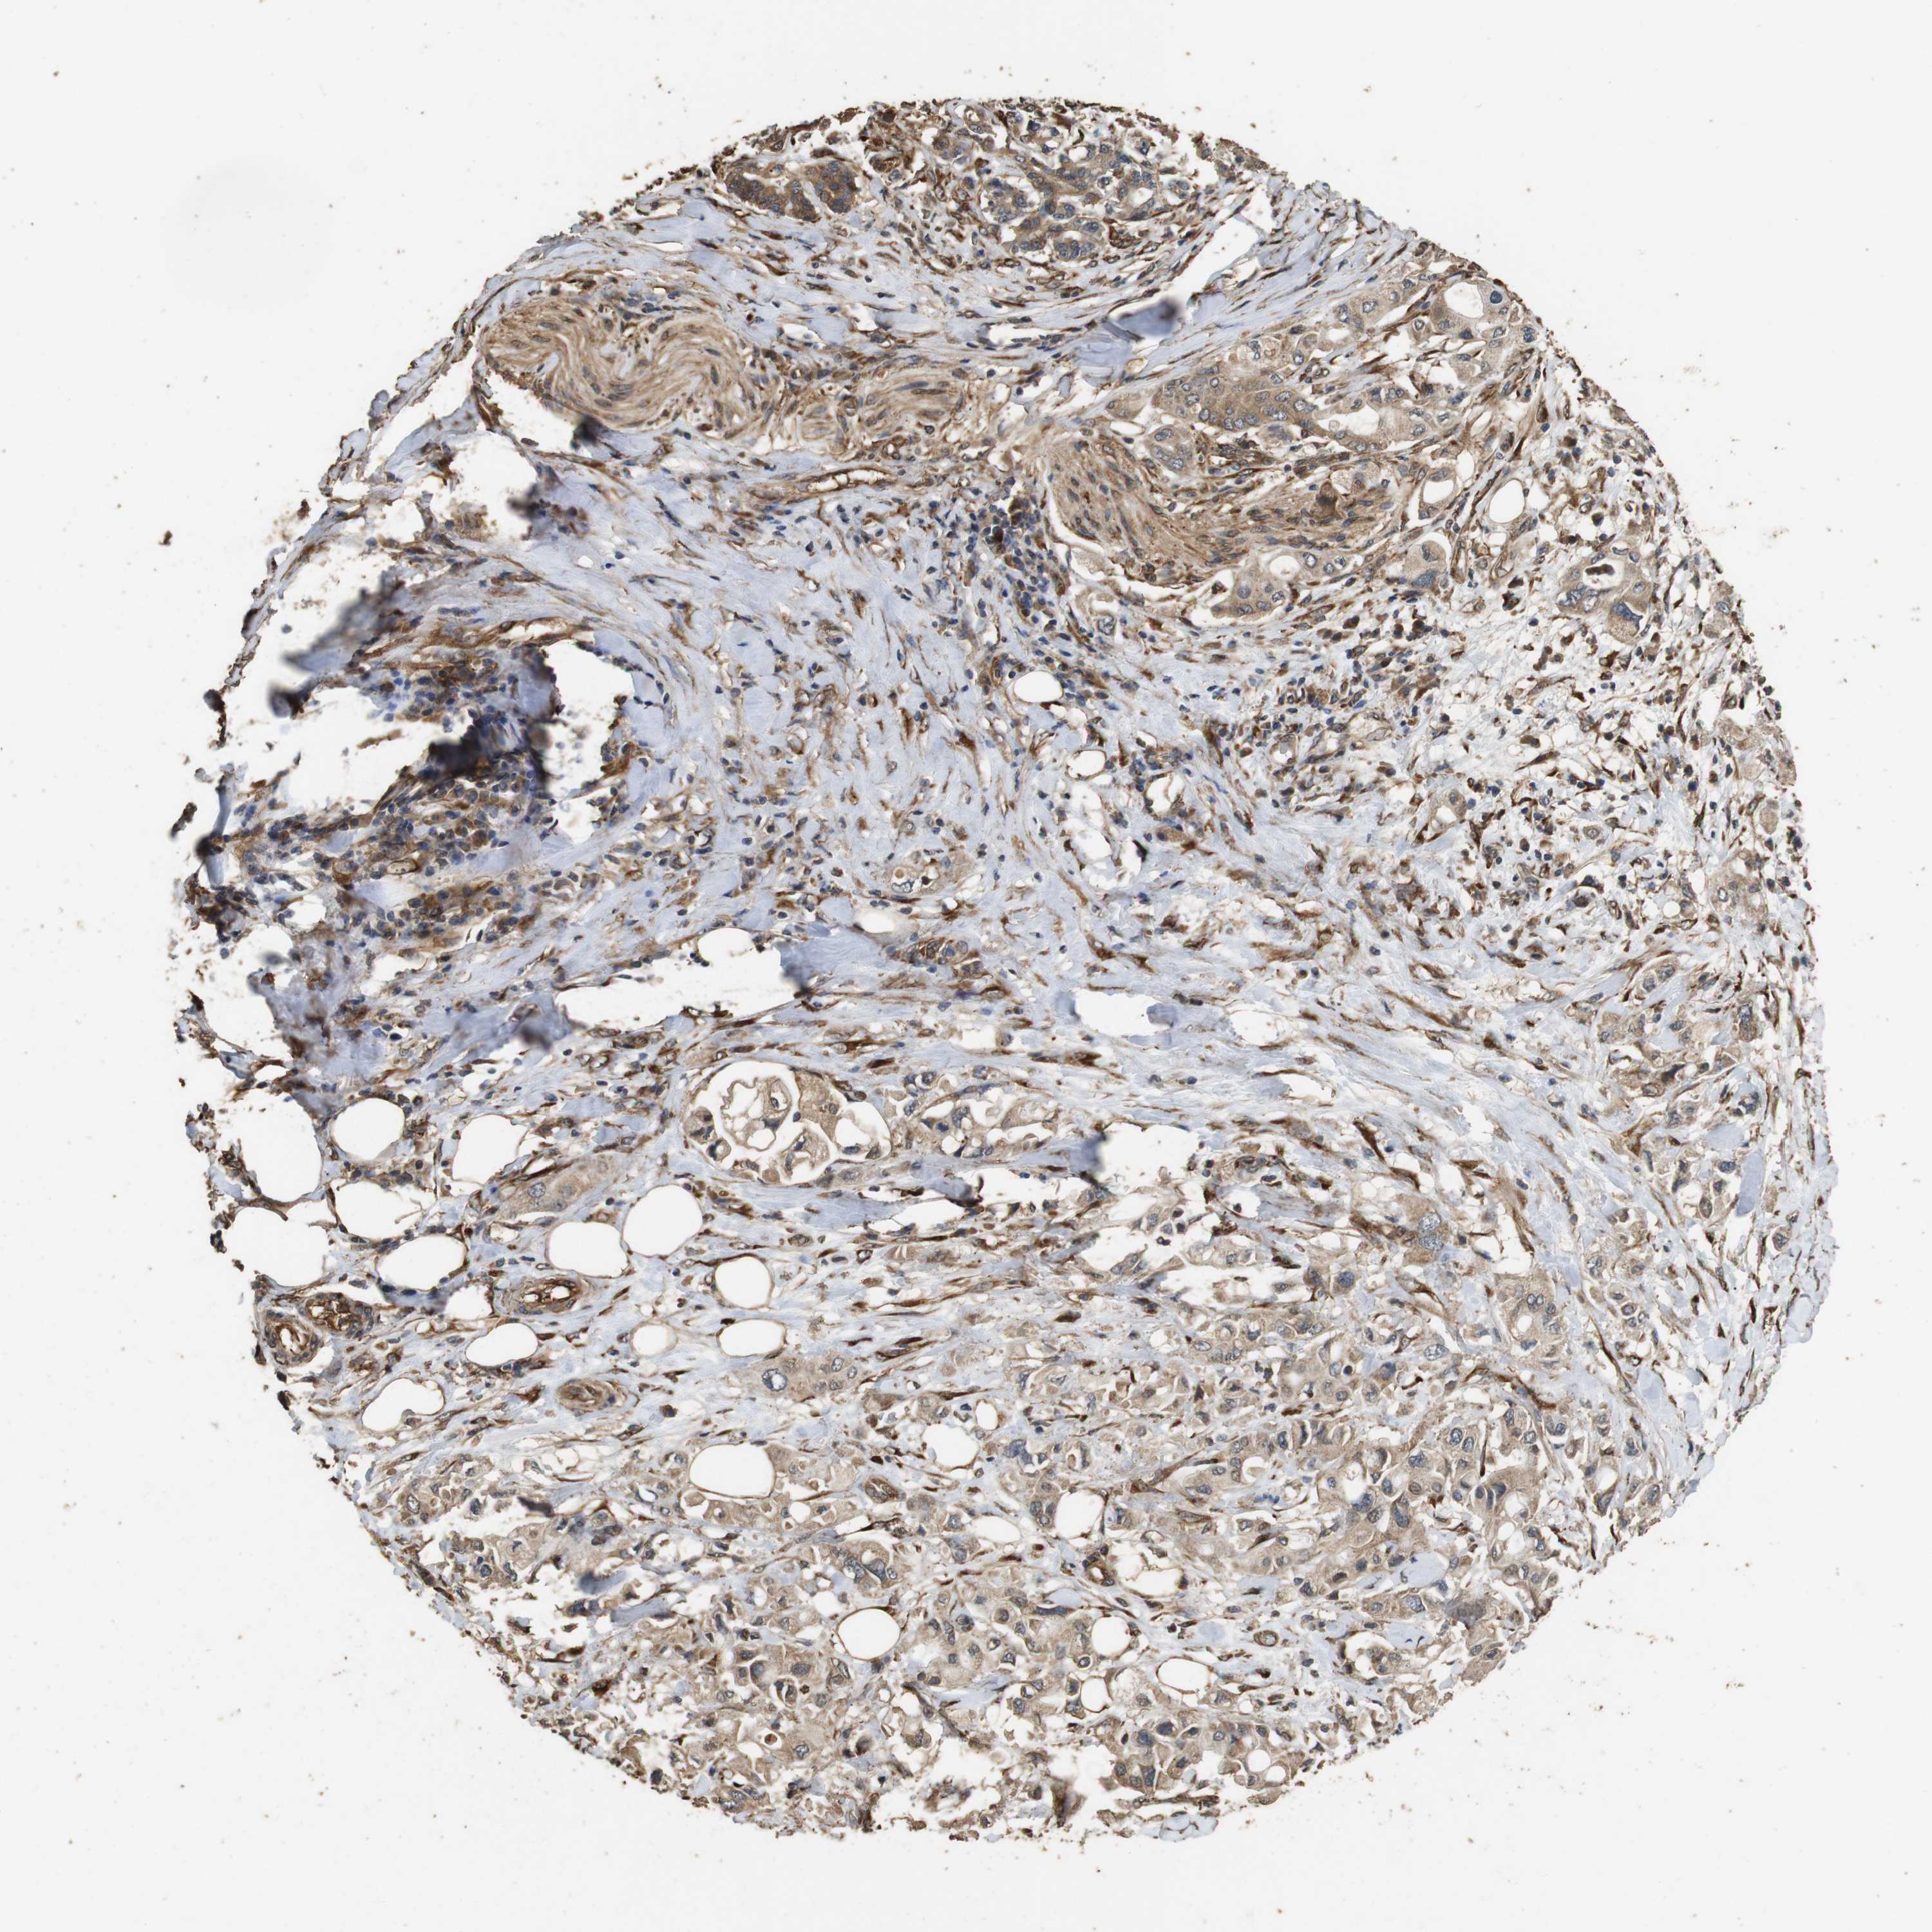

PANCREATIC CANCER - Protein expressioni

A mouse-over function shows sample information and annotation data. Click on an image to view it in a full screen mode. Samples can be filtered based on level of antibody staining by selecting one or several of the following categories: high, medium, low and not detected. The assay and annotation is described here.

Note that samples used for immunohistochemistry by the Human Protein Atlas do not correspond to samples in the TCGA dataset.

Antibody stainingi

Antibody staining in the annotated cell types in the current human tissue is reported as not detected, low, medium, or high, based on conventional immunohistochemistry profiling in selected tissues. This score is based on the combination of the staining intensity and fraction of stained cells.

Each image is clickable and will lead to virtual microscopy that enables deeper exploration of all samples and also displays staining intensity scores, fraction scores and subcellular localization as well as patient and tissue information for each sample.

Antibody HPA014166

Antibody HPA025240

Staining

High

Medium

Low

Not detected

Intensity

Strong

Moderate

Weak

Negative

Quantity

>75%

75%-25%

<25%

None

Location

Nuclear

Cytoplasmic/membranous

Cytoplasmic/membranous,nuclear

Adenocarcinoma, NOS

Adenocarcinoma, metastatic, NOS